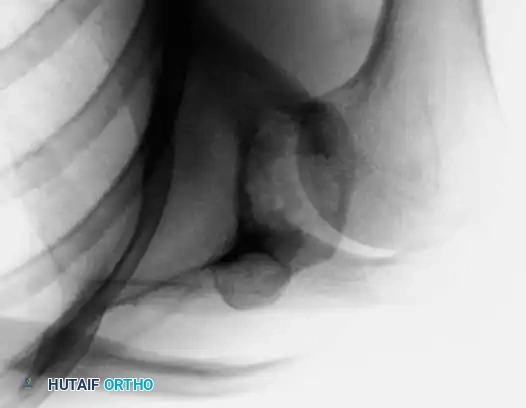

The radiographic appearance of adamantinoma is highly characteristic, though it must be carefully differentiated from other benign and low-grade malignant bone lesions. The classic presentation on plain radiography is that of multiple, sharply demarcated radiolucent lesions within the anterior tibial diaphysis.

These lytic areas are frequently separated by regions of dense, sclerotic bone, creating a multiloculated, "bubbly," or "soap bubble" appearance. The lesion is typically eccentric, expanding the anterior cortex, and may demonstrate cortical thinning or frank destruction.

A significant portion, or even the entire length, of the tibial diaphysis can be involved. Direct extension of the tumor into the adjacent fibula is a frequent finding (occurring in up to 15% of cases), necessitating careful evaluation of both bones during initial imaging. Standard orthogonal radiographic series (anteroposterior and lateral views) covering the entire tibia and fibula are essential.